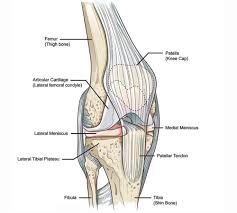

Methods sixteen knees with a small medial femoral. The femoral condyle is a thickened area of the femur just above the knee. What is an articular cartilage defect and how is it treated? The femur (thighbone), the tibia, (shin), and the patella (kneecap). Generally, ocd seems to affect males more commonly than females (between 2:1 and 3:1).

Lateral aspect of medial femoral condyle most common location. The motions of the condyles include rocking, gliding and rotating. In the knee, chondromalacia is usually related to injury, overuse of the knee, and poorly aligned muscles and bones around the knee joint. Methods sixteen knees with a small medial femoral. When ocd affects the knee, the most common location is within the lateral aspect of the medial femoral condyle. Medial condyle of femur from wikipedia, the free encyclopedia the medial condyle is one of the two projections on the lower extremity of femur, the other being the lateral condyle. The femoral condyle allograft has been used for resurfacing cartilage defects with mature hyaline cartilage for several decades, with very high success rates. The medial femoral condyle is supplied by a plexus of vessels from the descending genicular artery and the medial superior genicular artery.

A bone fracture at this location is termed a femoral condyle fracture. Tendons and ligaments attach your kneecap to your shinbone and thigh. What is an articular cartilage defect and how is it treated? This is associated with a positive bone scan and, frequently, a radiolucent lesion in the subchondral zone. Damage may also be the result of a direct blow to the knee.

The medial femoral condyle is supplied by a plexus of vessels from the descending genicular artery and the medial superior genicular artery. Medial condyle of femur from wikipedia, the free encyclopedia the medial condyle is one of the two projections on the lower extremity of femur, the other being the lateral condyle. This is associated with a positive bone scan and, frequently, a radiolucent lesion in the subchondral zone. Osteonecrosis of the medial femoral condyle presents as a sudden onset of pain on the medial side of the knee. Three bones meet within the knee joint: Cartilage can be focally damaged, producing a pot hole in the joint surface, when the knee ligaments are injured. Versatility of the medial femoral condyle flap for extremity reconstruction and identification of risk factors for nonunion, delayed time to union, and complications. Juvenile ocd lesions have a better healing prognosis than adults. The medial condyle is named for its location on the inside of the knee, closer to the midline of the body, while the lateral condyle is found on the outside of the knee, away from the midline of the body. One presumed mechanism of injury is a stieda fracture (avulsion injury of the medial collateral ligament at the medial femoral condyle). Methods sixteen knees with a small medial femoral. The motions of the condyles include rocking, gliding and rotating. Based on the patient's antalgic gait and radiographic findings, the patient was instructed on the proper use of crutches and referred to an orthopaedic surgeon for appropriate management.